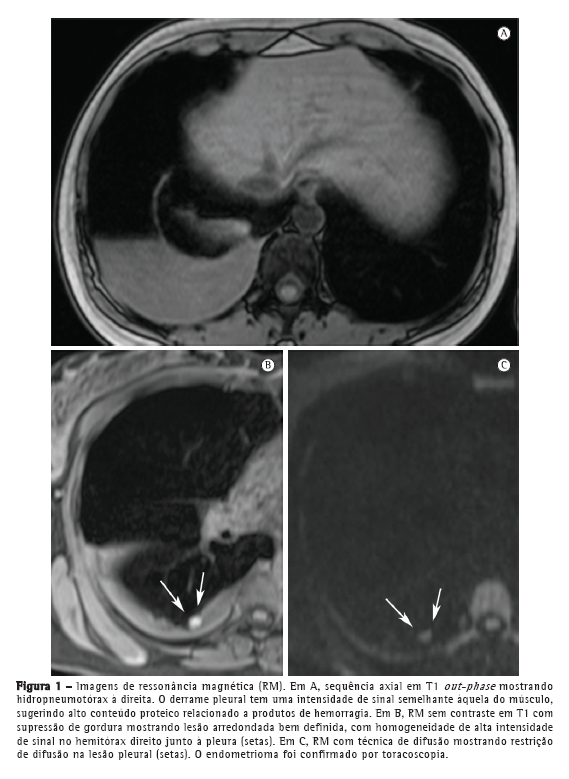

A paciente permaneceu assintomática por 4 anos. Aproximadamente seis meses antes do presente relato, a paciente apresentava dispneia cíclica, tosse seca e dor pélvica leve apesar do uso de contraceptivos orais. Uma radiografia e uma TC de tórax revelaram leve hidropneumotórax à direita. O parênquima pulmonar estava normal. Na RM de tórax em sequência T1 e T2, com e sem supressão de gordura, foi observado hidropneumotórax direito, e na RM em sequência T1 e supressão de gordura foram observadas lesões nodulares hiperintensas na pleura; algumas dessas lesões apresentavam difusão restrita (Figura 1), que é sugestiva de endometriomas.

Nos últimos anos, a RM de tórax progrediu muito. Devido a melhorias na velocidade e na qualidade das imagens, a RM está pronta para ser usada na rotina clínica.(7-9) Nos dois casos aqui apresentados, a RM de tórax revelou hidropneumotórax e nódulos arredondados bem definidos na superfície pleural do hemitórax direito. No Caso 1, o derrame pleural apresentou intensidade de sinal intermediária em T1, sugerindo alto conteúdo proteico, provavelmente relacionado a produtos da hemorragia. No Caso 2, o derrame pleural apresentou alta intensidade de sinal, sugerindo hemotórax recente. Os nódulos pleurais observados no Caso 1 mostraram homogeneidade na alta intensidade de sinal em imagens em T1 com supressão de gordura e difusão restrita em imagem ponderada em difusão (IPD). No Caso 2, os nódulos mostraram heterogeneidade na intensidade de sinal nas imagens em T1 e T2, sem restrição de difusão. De forma semelhante à endometriose pélvica,(1,10) os nódulos pleurais da endometriose torácica podem mostrar diferentes intensidades de sinal em imagens em T1 e T2, assim como na variação de restrição de difusão, dependendo da idade da lesão.